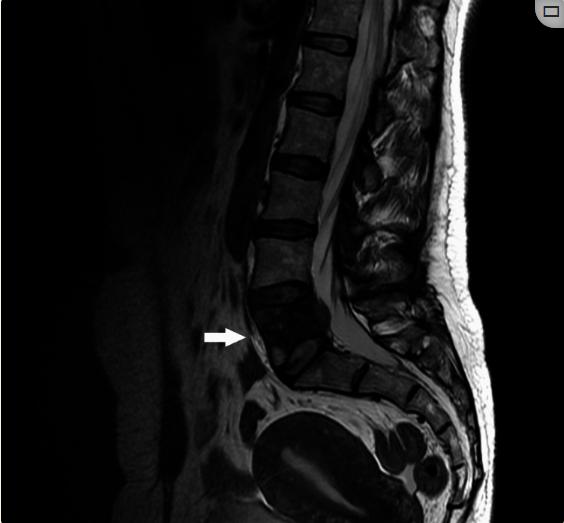

患者女性,46岁,高加索人,于2020年9月就诊,左下肢放射性腰痛史1年,八个月内体重减轻10%以上。背腰触诊没有发现任何异常或引起任何局部疼痛。神经病学检查,拉塞格征阳性,左脚伸展受限。在这种情况下,对患者进行了CT扫描,显示了一个28.3毫米的损伤,涉及身体、左椎弓根和L5椎骨的左上关节面(图1, 2)。在磁共振成像(MRI)上,病变在T1WI和T2WI上呈低信号,在T2加权短时反转恢复序列(STIR)上没有信号变化,并且具有异常的对比度增强(图3--6)。该病变与左侧椎旁软组织肿块相关,并伴有椎管内和椎间孔表现,该肿块覆盖了硬膜外腔的左侧前外侧和左侧L5-S1椎间孔,可能伴有左侧L5神经根压迫。为了排除远处转移,还对患者进行了PET/CT ,显示左侧L5出现高代谢恶性病变(图7)。

图4、核磁共振,T2WI序列

在MRI上,病变在T2WI上呈等信号